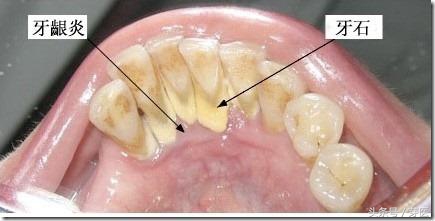

洗牙,口腔科专业术语叫“龈上洁治术”,是指用洁治器械去除牙龈上牙石、菌斑和色渍,并磨光牙面,以延迟菌斑、牙石的再沉积。牙菌斑、牙结石是发生牙周病的最主要局部刺激因素,而洁治术是去除龈上菌斑、牙石的有效方法,搅乱了牙菌斑的膜结构,从而减少了细菌的增殖、堆积。

长时间不洗牙,刷牙又不彻底,牙菌斑大量堆积,还会形成牙石,这不但危害牙齿、牙龈而且慢慢的牙槽骨还会发生萎缩,牙槽骨萎缩会连累牙龈一起“后退”,牙根也就暴露了,但由于暴露的牙根被牙石等覆盖着暂时没有被发现。所以,洗牙后牙菌斑、牙石被清除,一时间就会感觉牙齿酸、牙缝“变大”了。所以,越是尽早开始有规律地清洁牙齿,越不会出现牙根裸露酸痛的问题,发生牙周病的几率也会减少。